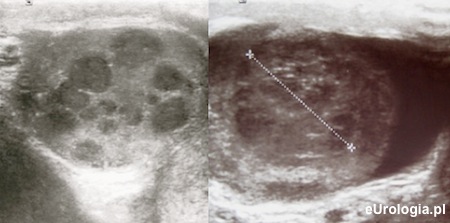

USG moszny jest nieinwazyjnym badaniem wykonywanym w przypadku podejrzenia jakiejkolwiek patologii w obrębie moszny. Badanie jest niebolesne i polega na ultrasonograficznej ocenie jądra, najądrza i powrózka nasiennego. Badanie USG jądra wykonywane jest głowicą liniową i jest złotym standardem w diagnostyce obrazowej nowotworów jądra. Badanie USG w diagnostyce nowotworów jądra charakteryzuje się blisko 100% czułością.

Fot. Przykłady guzów jądra w badaniu USG.